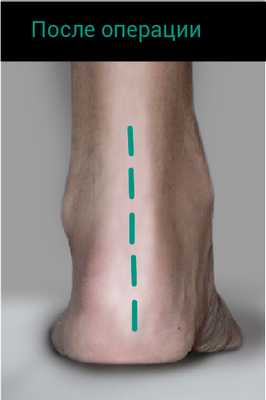

После операции больному наложена гипсовая лонгета по передней поверхности левой голени от верхней трети до кончиков пальцев с углом подошвенного сгибания в голеностопном суставе 20°. Рекомендовано: ходьба без опоры на левую ногу до 5 нед. Затем проходил курс восстановительного лечения.

В результате через 3 мес пациент смог поднять вес своего тела на двух стопах, а через 6 мес — поднять вес своего тела на одной стопе.

По результатам подометрии через 6 мес после операции ассиметрии походки не выявлено. Сила мышц подошвенных сгибателей стоп (по шкале Ловвета): справа — 5 баллов, слева — 5 баллов. Результат хирургического лечения у пациента П. оценен как хороший.